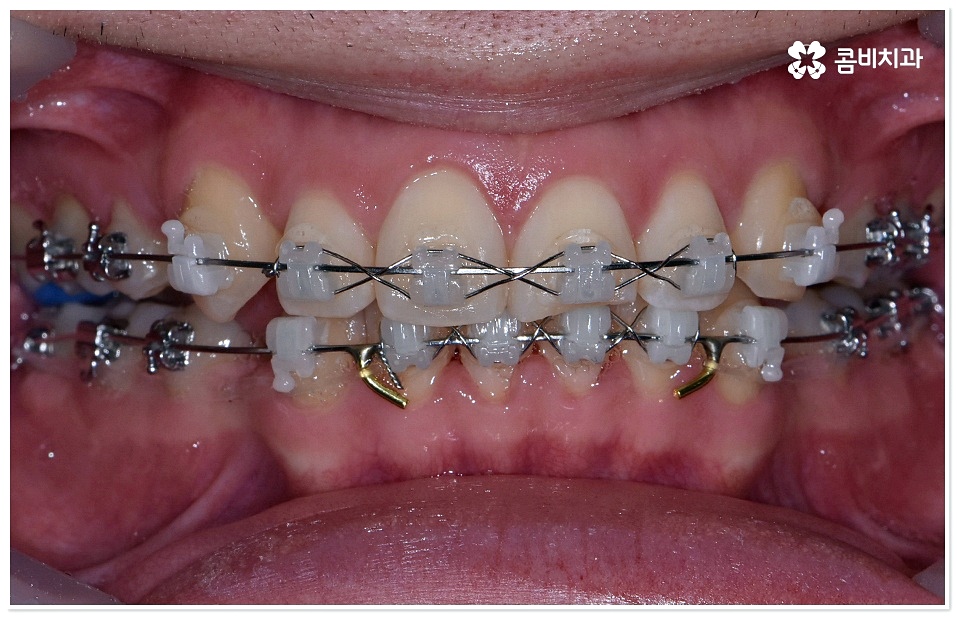

하지만 막상 덧니치아교정 을 받고 싶어도 실제로 시작하기까지 여러 가지 망설여지는 포인트가 있으실 거예요. 그 중에서도 겉으로 드러나는 장치 때문에 부담을 느끼시는 분들이 있을 수 있는데 최근에는 관련 의료 기술이 발전하면서 교정 장치가 눈에 덜 띄도록 하는 방법과 장치들이 나와 환자분들이 느끼시는 심미적인 부담을 줄여주고 있으니 먼저 검진 및 상담부터 받아보시길 권유드리고 있어요. 특히 교정치료 기간 동안 스스로 탈착이 가능한 투명교정 등 환자의 상태에 맞춘 다양한 방법을 알아볼 수 있으니 숙련된 의사선생님과 충분히 상담한 후 자신에게 적합한 계획을 세우실 필요가 있어요.

교정 치료란 특수한 장치를 이용해 치아를 원하는 방향으로 이동시켜 치아 배열과 교합을 올바르게 개선해 주는 과정으로 각자의 구강 구조가 다 다르기 때문에 정밀 검사를 통해 환자분들 각각의 치아 모양과 각도, 위치, 교합 뿐 아니라 잇몸 건강 상태 및 상악과 하악의 관계와 같은 구강 내 상황과 함께 입술, 전체 안모 등 대칭과 균형의 측면에서 모든 부분을 다각적이고 입체적으로 분석한 후 세밀한 맞춤 계획을 수립하는 것이 중요할 수 있는데요.

덧니치아교정 치료를 받으시는 분들 중에서 혹시 통증이 있어야 치아 이동이 좀 더 잘 되는 것이 아닌가 문의를 주시는 분들이 있는데, 통증이 없더라도 치아에 일정한 힘이 계속해서 작용하기 때문에 담당 의사의 치료 계획에 맞춰 치아는 지속적으로 이동하며, 통증이 있어야만 치아가 잘 이동하는 것은 아니고 오히려 치아에 일정 수준 이상의 무리한 힘으로 이동시킬 경우 부작용이 발생할 수 있기 때문에 주의하실 필요가 있습니다. 치아가 이동하는 원리를 살펴보면 교정 치료 중 일정 방향으로 치아에 힘이 가해지면서 치아를 감싸고 있는 치주인대가 일시적으로 늘어나 해당 부위의 잇몸뼈가 흡수되고 반대쪽으로 새롭게 잇몸뼈가 생성되는 생물학적인 대사 과정을 통해 치아가 움직이는 것을 알 수 있는데, 이렇게 조금씩 치열을 바로잡아 나가는 과정 중에 환자분들의 다양한 상황이 회복력에 영향을 주게 되기 때문에 전체 교정 기간은 저마다 차이가 나게 되는 거예요.